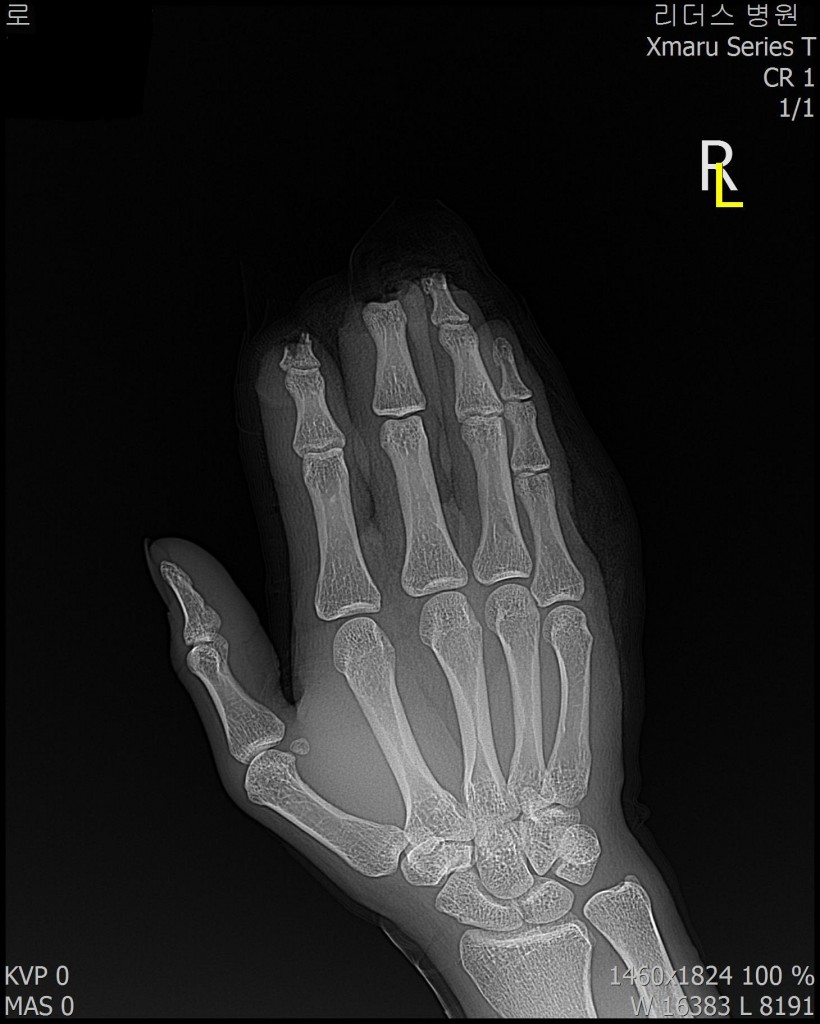

2018, 1월 1일 수지접합 ( 좌측 2,3,4수지 말단전달 치료 전, 후 모습)

2018 / 11일 당시 ( 외국인 로 **)께서 좌측 2,3,4수지 말단전달본원 방문하여